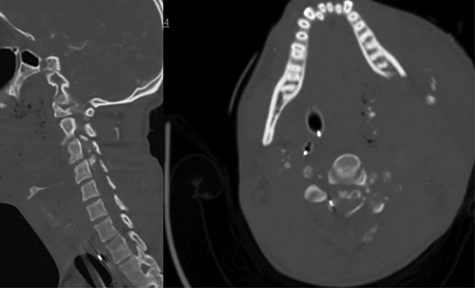

A 39-year-old African–American male presented with a gunshot wound through the right neck. The patient suffered a comminuted C6, C7 and T1 fractures with suspected right vertebral artery injury (Fig. 3). The patient was taken emergently to the operating room by the trauma surgery team for emergent neck exploration, right external jugular vein ligation and partial wound closure. The patient was noted to have a C4 ASIA A spinal cord injury. On hospital Day 2 the patient underwent a digital subtraction angiogram and embolization of a right vertebral arteriovenous fistula. On hospital Day 3, the patient was noted to have a CSF leak. Despite additional attempts to achieve a wound closure and several days of conservative management, the csf leak persisted. We decided to place an EVD because the spinal canal at c6/7 appeared completely obliterated.

CT cervical spine; sagittal (left): demonstrates comminuted c6, c7 and T1 fractures, and the axial (right) demonstrated complete spinal obliteration with bullet and bone fragments at the C6/7 level.